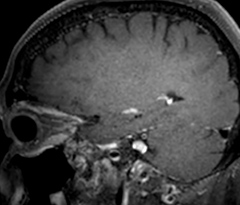

This is an example of acute ischemic stroke with distal occlusion of the right posterior cerebral artery. Note the improved visibility of the ischemic territory on the diffusion weighted image with high b-value. The 3D FLAIR shows a distal PCA occlusion. The fast SWIp depicts the thrombus on the isolated second echo image. The total scan time (including SmartBrain, preparations and a fast 3D T1w TSE Gd) is 8:00 minutes.